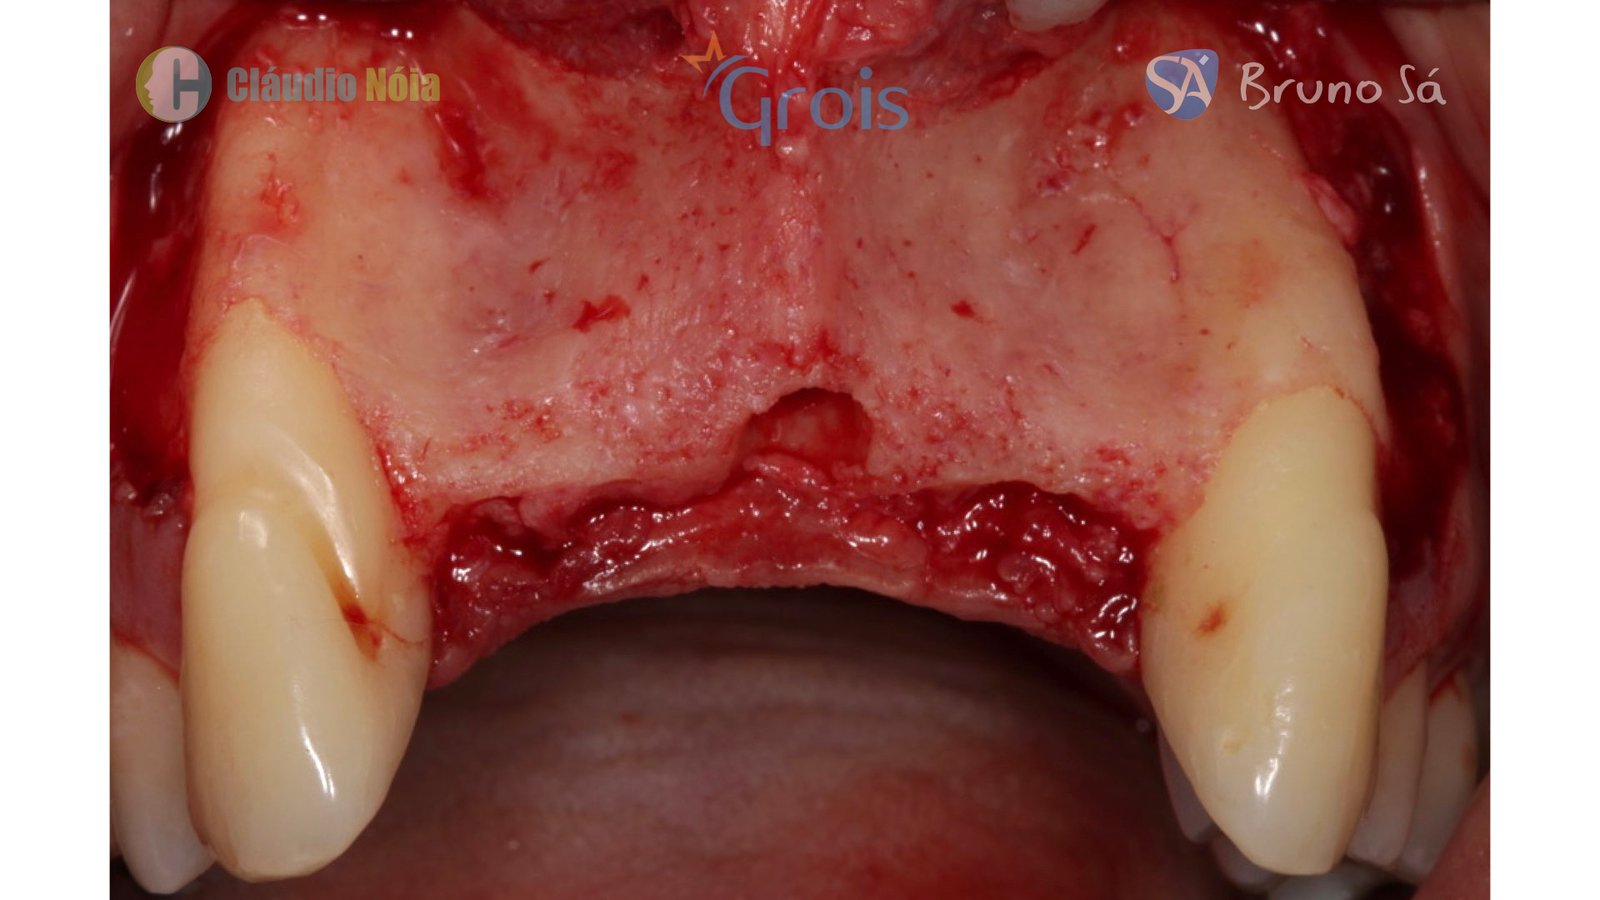

O bom posicionamento dos implantes é pré-requisito fundamental para obtenção de uma reabilitação implantossuportada adequada aos pacientes. No entanto, para se alcançar esse posicionamento tridimensional ideal dos implantes é necessária quantidade e qualidade óssea no leito implantar. Em situações que o remanescente ósseo é insuficiente, torna-se necessário o emprego de técnicas reconstrutivas, e dentre elas estão técnicas como enxerto autógeno em bloco, osteotomias expansivas como a técnica Split Crest, regeneração óssea guiada e técnica Screw Tent Pole.

Paciente apresentou-se a Área de CBMF da Instituição com a pré-maxila edêntula (Figuras 1, 2 e 3) e foi submetido a técnica Screw Tent Pole utilizando os parafusos da linha Orth – Implacil de Bortolli (Figura 3). Do lado direito da pré-maxila foram instalados 3 parafusos que apresentavam roscas em toda superfície, enquanto que do lado esquerdo foram instalados 3 parafusos que não apresentam roscas no terço cervical (Figuras 4, 5, 6, 7 e 8). Biomaterial associado com PRF (Stick Bone) foi adequadamente acomodado na região e recoberto por membranas de PRF (Figuras 9, 10 e 11). Uma sutura livre de tensão foi realizada para finalizar o procedimento cirúrgico (Figuras 12 e 13).